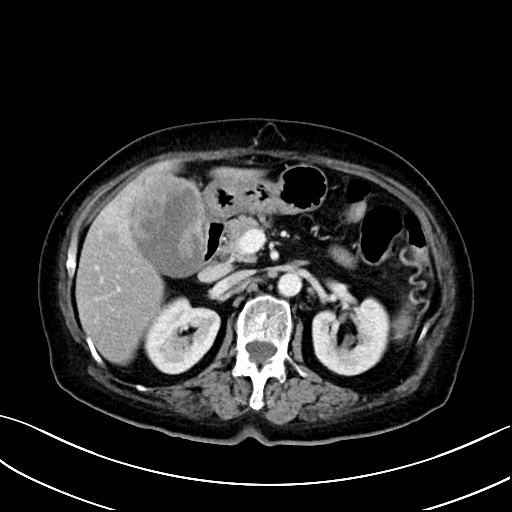

70多岁的王女士就是其中一位。2021年,王女士诊断为胆囊癌侵犯肝脏、腹壁,初始评估无手术机会,在潞河医院肿瘤中心经过精准抗肿瘤内科治疗(抗HER-2靶向药物联合PD-1单抗)后获得了手术切除机会,术后病理提示未见残存肿瘤细胞,目前处于无瘤生存状态。

治疗前